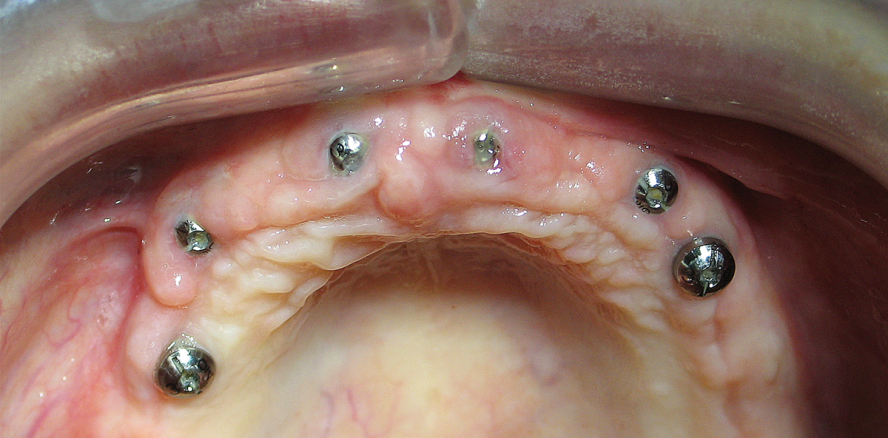

Bei allen Systemen waren die abgewinkelten Abutments zweiteilig. System B und C bieten bei den geraden sowohl ein- als auch zweiteilige Komponenten an. C-Komponenten sind mit einer Einschnapp-Funktion erhältlich, welche das Einbringen erleichtert. Fast alle Systeme haben einen Rotationsschutz zwischen Abutment und Implantat. Implantate ohne Rotationsschutz müssen bei der ersten Einprobe im Mund verbleiben. Als vorteilhaft erwies sich auch ein Rotationschutz zwischen Abutment und Sekundärkappe, welcher nicht bei allen Systemen vorhanden ist. Besonders bei Typ B war das Einbringen der Abutments zeitaufwendig. Die mit den Abutments oft gelieferten Einbringhilfen reichten zum Einsetzen der Arbeiten nicht aus. Nur bei Typ D waren keine zusätzlichen Instrumente erforderlich. Auffällig war die vorteilhafte Form der Komponenten von Typ C. Durch die konkave Gestaltung des Emergenzprofils bietet es dem Weichgewebe Platz und reduziert einerseits die Gefahr von Rezessionen (Pseudorezessionen) und andererseits formt es eine Zahnfleischmanschette um den Implantathals. Letzteres schützt den krestalen Knochen und verhindert das Durchschimmern der grauen Titanoberfläche. Die Abutments werden in Abbildung 1 bis 7 dargestellt.

In diesem Fall erschien die Patientin mit Röntgenbildern zur Beratung. Nach einer chronischen unbehandelten Parodontitis wurden alle Zähne als nicht erhaltungswürdig eingestuft. Die Implantation erfolgte verzögert – sechs Wochen nach Extraktion. Nach der Freilegung bei der ersten Einprobe waren optimale Weichgewebeverhältnisse zu sehen. Der Oberkiefer wurde keramisch und der Unterkiefer kunststoffverblendet restauriert (Abb. 8–18).

In diesem Fall war die Situation fast identisch mit Kiefer 5 und 6. Der Oberkiefer wurde keramisch verblendet. Die gute Platzierung der Implantate erlaubte, auf geneigte und kurze Implantate zu verzichten. Quantität und Qualität der keratinisierten Gingiva gewährleisten langfristige Ästhetik und Gewebestabilität (Abb. 19–23). Anschließend wurden im teilbezahnten Unterkiefer die Zähne 42, 32, 36, 44 und 47 extrahiert und in Regio 32, 36, 44 und 46 implantiert. Die Patientin bekam festsitzende Restaurationen.